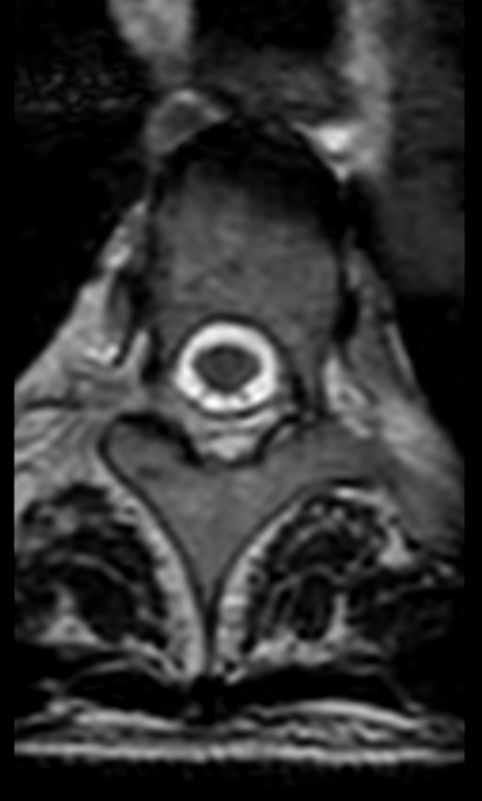

3D T2w TSE (SpineVIEW) - Axial reformatCompressed SENSE